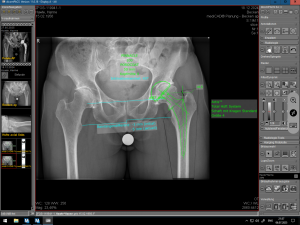

(Bilder: 1-3 Röntgenbild vor der OP mit Arthrose der linken Hüfte,

Digitale Prothesenplanung, Röntgenbild nach der OP)